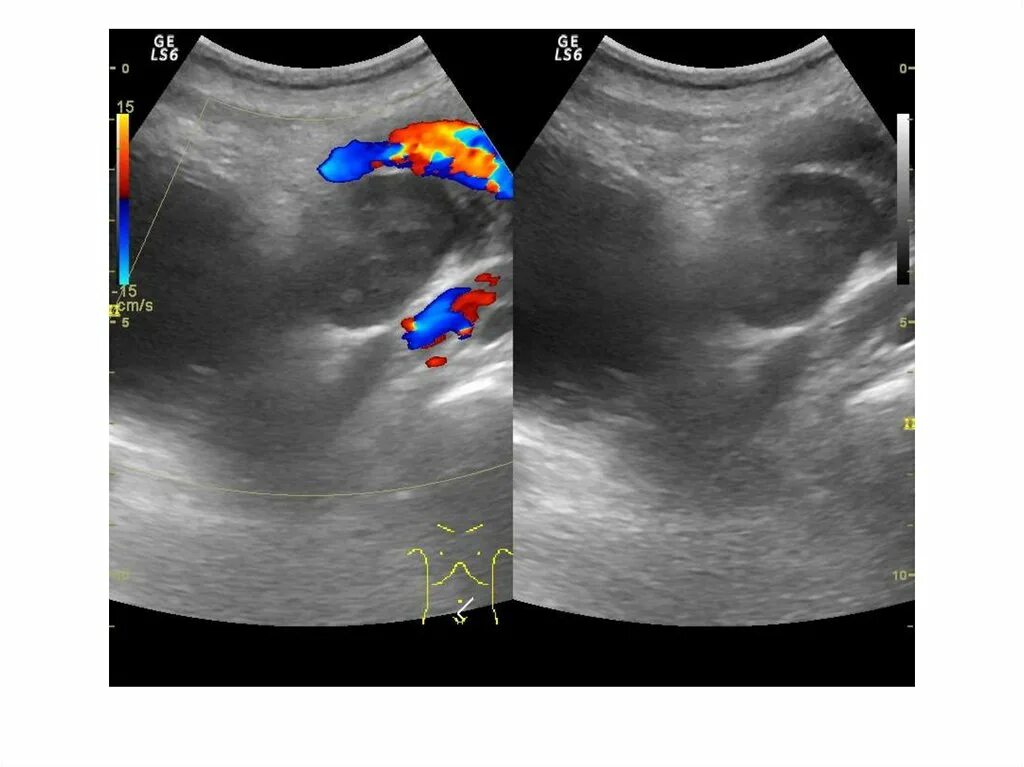

Простатит везикулит